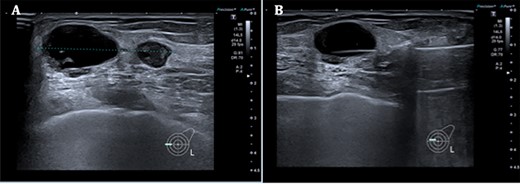

A. Left breast ultrasound showing two lesions at the 9 o’clock position measuring a total distance of 37 mm. B. Core biopsy done of the main lesion.

Triple assessment was done—examination revealed multiple cutaneous neurofibromas in keeping her NF1. Breast examination revealed a firm irregular 2-cm lump at the 9 o’clock position of the left breast with no contralateral lumps nor any evidence of lymphadenopathy. Bilateral mammogram demonstrated a dense indeterminate mass on the left breast (Fig. 1). Targeted ultrasound scan showed two cystic-like lesions adjacent to each other (Fig. 2). A core needle biopsy was done of the larger lesion confirming grade 3 invasive ductal carcinoma—receptor status analysis revealed that the lesion was ER negative, PR negative and HER2 positive.